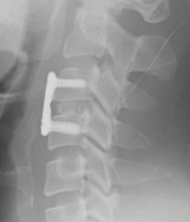

목 디스크의 수술 방법은 크게 4가지 수술법이 있습니다.